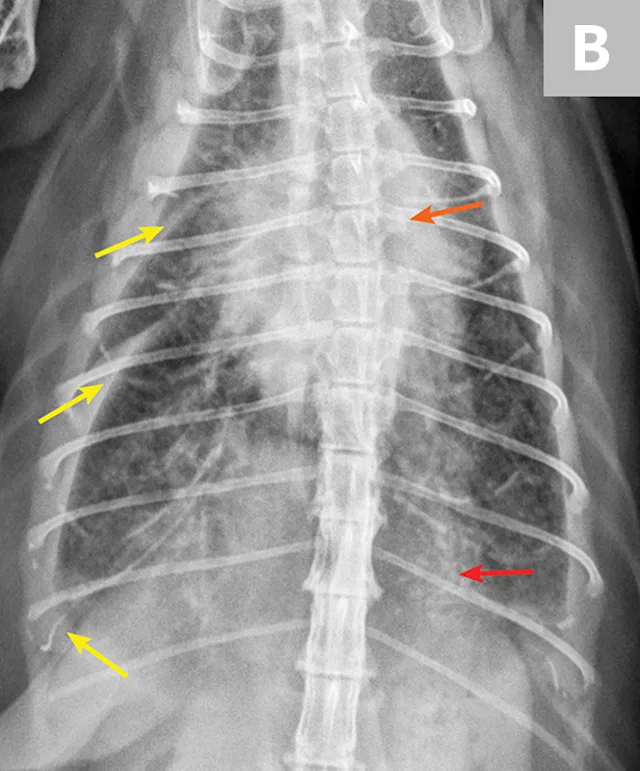

Overt cardiomegaly may be understated on radiographs because of changes in internal diameter that do not affect the overall cardiac silhouette. Vertebral heart score >9.3 supports a CHF diagnosis.1 Pulmonary venous congestion can be absent, and pulmonary arterial distension may be appreciated. The presence of pleural effusion with simultaneous pulmonary infiltrates is supportive of CHF (Figure 1).2

Congestive heart failure. Note the pleural effusion (arrows).